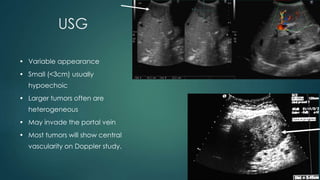

USG

• Variable appearance

• Small (<3cm) usually

hypoechoic

• Larger tumors often are

heterogeneous

• May invade the portal vein

• Most tumors will show central

vascularity on Doppler study.